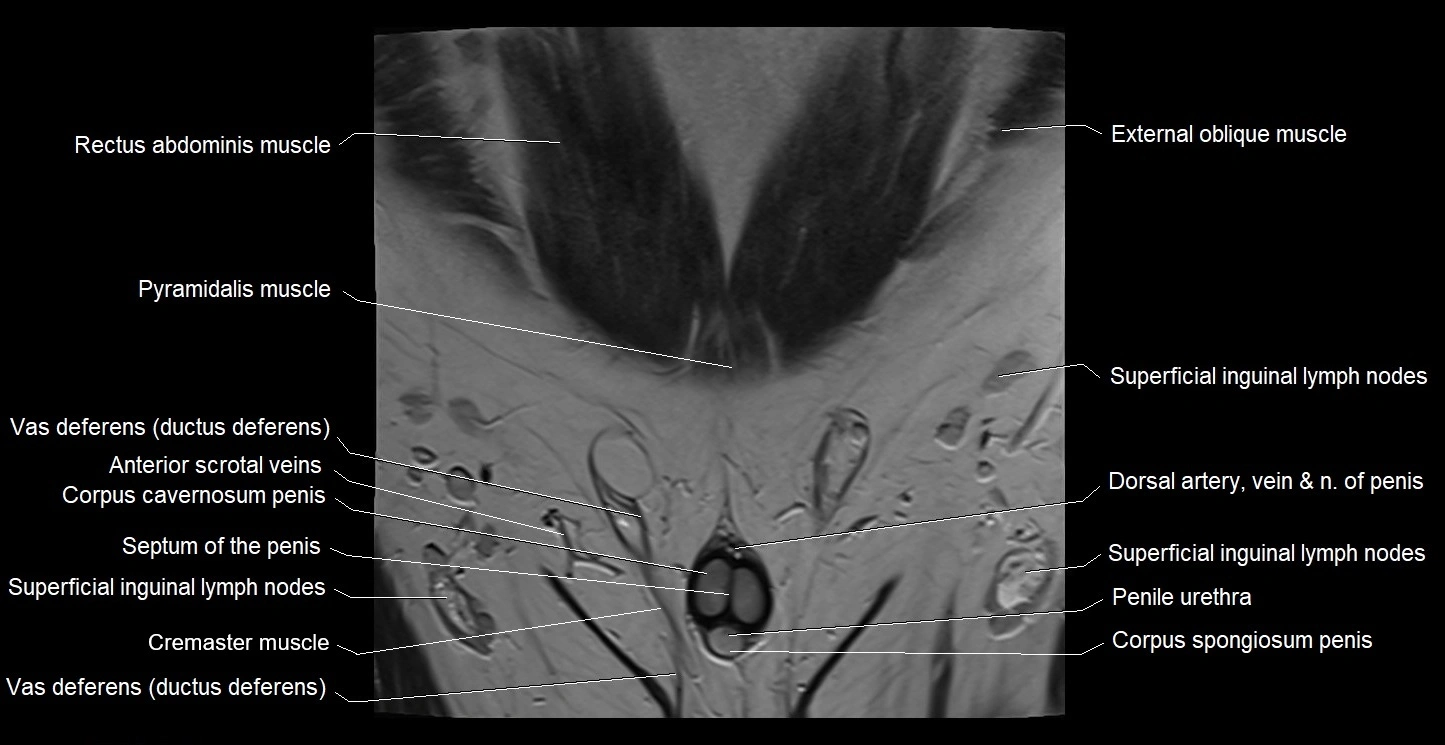

- Corpus cavernosum

- Corpus spongiosum

- Cremaster muscle

- Deep femoral artery (profunda femoris)

- Penile urethra

- Pyramidal muscle (pyramidalis muscle)

- Septum of the penis (Penile septum)

- Superficial inguinal lymph nodes